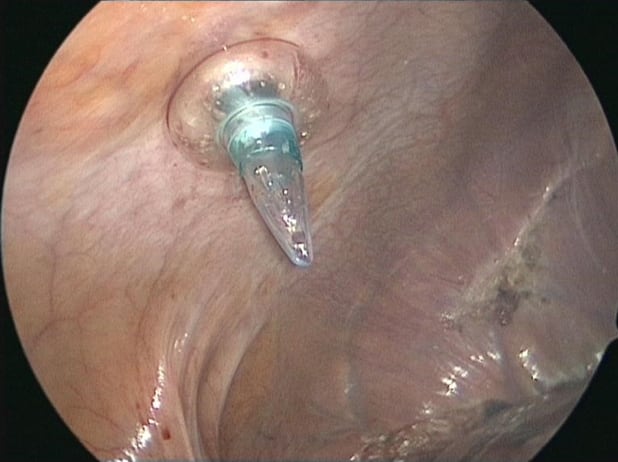

Intercostal port for anatomical segment 7 resection

Placement of stay suture